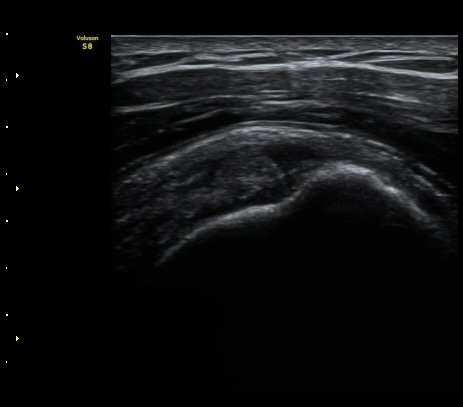

±ÙÀ§ºÎ ±Ø»ó°Ç Ⱦ´Ü¸é°Ë»ç¿¡¼­ ±Ø»ó°Ç ³»ÃøÀÇ ±¹¼ÒÀû Àú¿¡ÄÚ ºÎÁ¾À» º¸ÀÓ

(focal hypoechoic swelling at medial portion of supraspinatus tendon with transverse scan) »çÁø 7